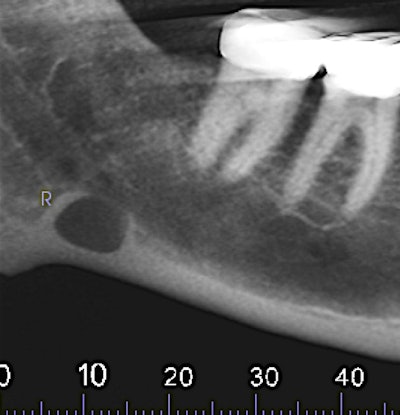

The oral surgeon ordered a cone-beam CT (CBCT) exam. Click images below to enlarge. In order: reformatted panoramic radiograph and cropped image of the area of interest, coronal view of the posterior right mandible (the inferior alveolar canal in red), and 3D reconstructed image of the posterior right mandible.

Figure 3: Coronal view of the posterior right mandible (the inferior alveolar canal is highlighted by red dot).

There is a hypodense lesion (radiolucent) that is well-defined, well-corticated, oval in shape, 8 x 6 mm, located at the posterior right mandible, and distal to tooth #32. The lesion is located below the inferior alveolar canal. No expansion is observed in the cross-sectional views. No calcifications are observed inside the lesion.

From the radiographic perspective, Stafne bone defects are radiolucent lesions, well-defined and well-corticated, oval in shape, and located below the inferior alveolar canal. No expansion is usually observed in the coronal views.